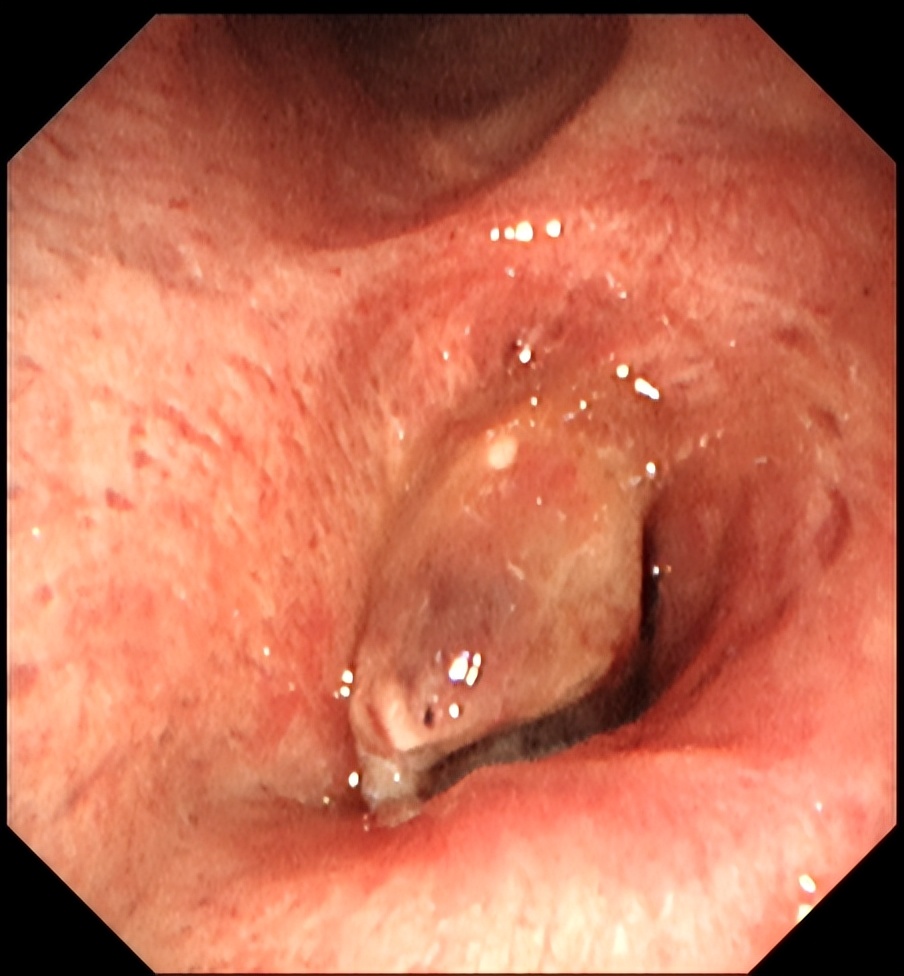

近日,北大医院太原医院(太原市中心医院)呼吸与危重症医学科汾东病区介入团队成功为一例肺癌致右主支气管完全梗阻,伴右肺不张的80岁高龄患者实施了经气管镜的肿瘤微波消融治疗术,手术成功打通右主支气管,保障患者通气功能,并置入Y型支架,防止肿瘤生长再次堵塞气道。术后,患者呼吸困难的症状得到改善,生存质量明显提高。

▲术前气道梗阻